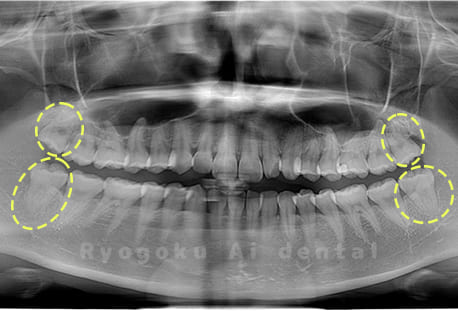

Case04

-

- 原因

- 上顎の親知らず、下顎の水平埋伏の親知らず

- 治療内容

- 上顎の親知らず、下顎の水平埋伏の親知らずを抜歯したケースです。

<リスク・副作用>

手術後は痛み、腫れ、痺れなどの副作用が生じる場合があります。